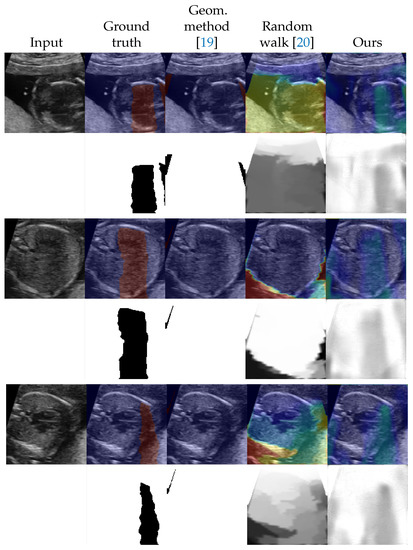

| Number of Labeled Images | |||||

|---|---|---|---|---|---|

| Method | 0 | 42 (5 Videos) | 90 (10 Videos) | 177 (20 Videos) | 259 (30 Videos) |

| Geometric method [19] | 0.152 (±0.182) | - | - | - | - |

| Random walk [20] | −0.047 (±0.290) | - | - | - | - |

| U-Net [30] | - | 0.308 (±0.150) | 0.267 (±0.144) | 0.262 (±0.158) | 0.247 (±0.172) |

| Ours | 0.351 (±0.155) | 0.388 (±0.150) | 0.414 (±0.159) | 0.358 (±0.149) | 0.349 (±0.162) |